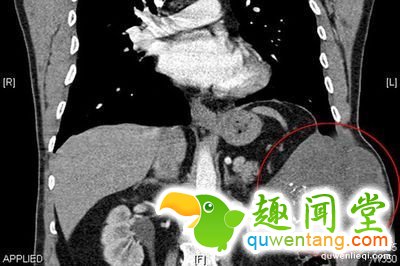

2、10厘米长匕首“藏”在胸腔,七年浑然不知

2006年,12月,在市中西医结合医院外科病房里青年陈某在病床上拿出了藏在他胸腔里7年的半截匕首,据了解,7年来,他并没有感觉不适,后来因为感冒才检查出来身体有匕首!